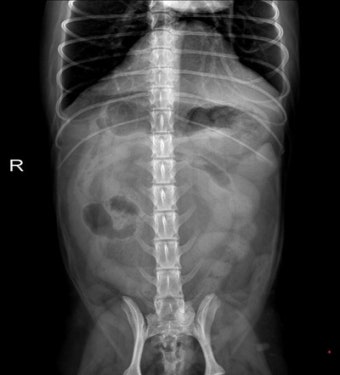

7. 이물질 삼킴으로 인한 구토

장난감 조각, 뼈 조각, 플라스틱 같은 이물질을 삼켰을 경우 몸이 그것을 배출하려고 구토를 유도합니다. 이때는 억지로 빼려 하기보다는 병원에서 X-ray 촬영이 필요합니다.